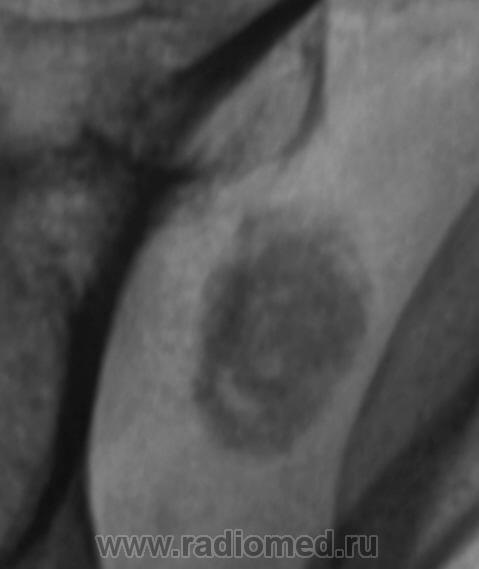

Пол пациента: Мужской пол Тип патологии: Доброкачественное новообразование, киста Область исследования: Скелетно-мышечная система Методы исследования: Rg При обследовании пациента - рентгенологическое исследование органов грудной полости выявлен "патологический процесс" лопатки. Ваше мнение коллеги? Thu, 10/09/2009 - 20:48 #1 tatyana Offline Last seen: 4 years 6 months ago Joined: 24.06.2009 - 08:33 Posts: 2090 если изменения в лопатке (а локализацию, я полагаю, Вы, Валентин Львович, уже установили при рентгеноскопии ) - хондрома или остеома; если в мягких тканях - хондромное тело или обызвествленный л/узел "самоуверенность дилетантов - предмет зависти профессионалов" Thu, 10/09/2009 - 21:05 #2 Катенёв Валенти... Offline Last seen: 7 years 5 months ago Joined: 22.03.2008 - 22:15 Posts: 54876 Образование интимно связано с лопаткой, проверил - поставил пациента за екран.

Образование интимно связано с лопаткой, проверил - поставил пациента за екран.